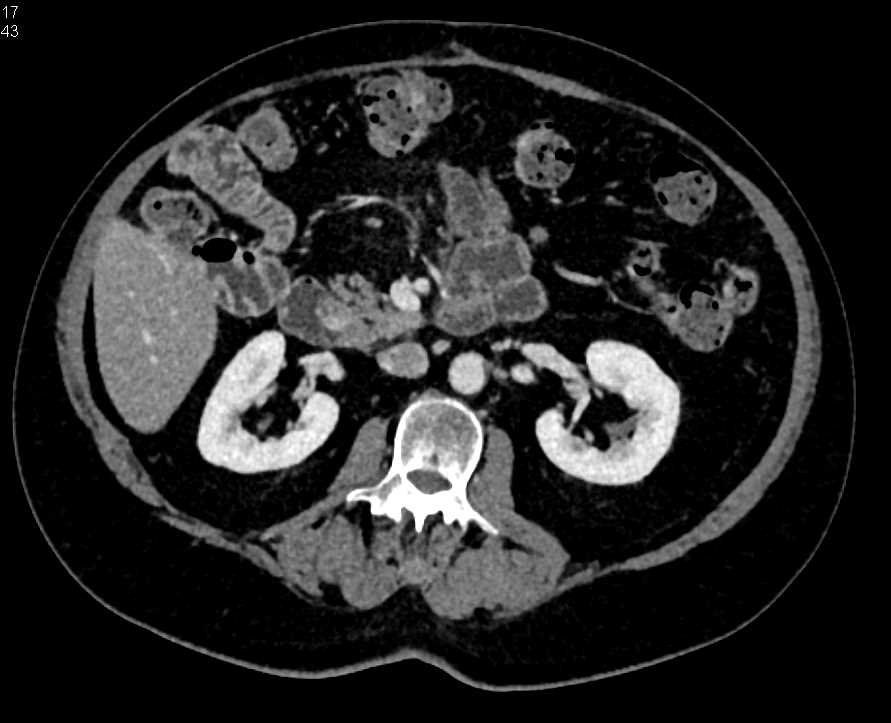

Duodenal Adenocarcinoma with Spread Into the Mesentery